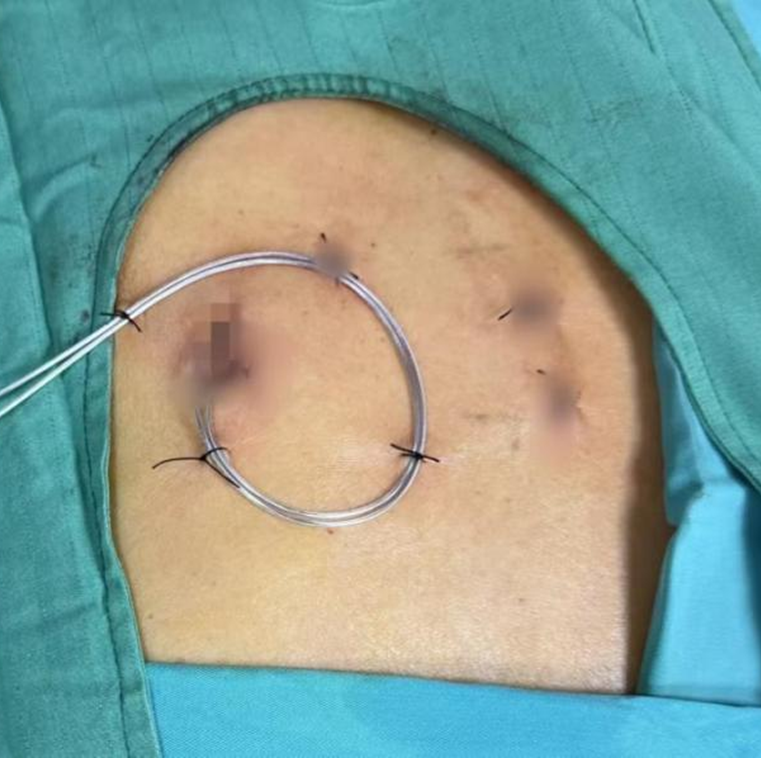

手术在高倍显微镜下完成,无需开颅,仅通过颈部微创切口,将健康一侧的颈7神经精准移位、吻合到瘫痪侧上肢神经,让健侧大脑同时控制双侧肢体,绕开受损的大脑半球,重新建立运动指令通路。

医生在影像引导下,通过毫米级微小切口,将微型电极精准植入脊髓硬膜外间隙,连接皮下脉冲发生器,释放温和电脉冲。